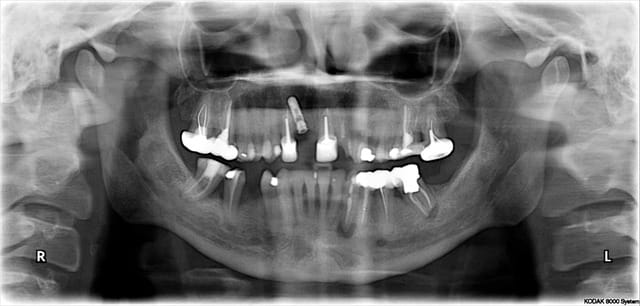

Céramik comme promis Ma réponse en image 2ans après

Est ce l'échec affirmé par certains?

1 Pano du cas

2 Pano qui a déclenché tous ces gentils commentaires

5 Pano aujourd'hui (le secteur 4 fichu???)